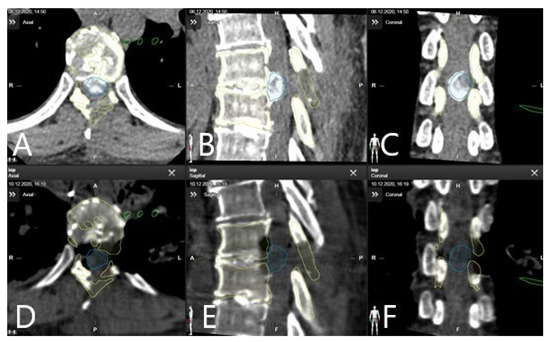

| 7 | L-Spine 70% | 12.34 | 192.00 | 167.04 | 167.00 | 179.38 | 3.55 | vertebral body replacement, screws and rods, T12, L1, L2, L3, L4, |

| 8 | T-Spine 70% | 35.59999 | 300.00 | 164.75950 | 188.00 | 200.36 | 3.57 | spinal cord, spinal canal, C1, C2, C3, C4, C5, C6, C7, T1, T2, T3, T4,T5, T6, T7, T8, T9, T10, T11, T12, disc hernation |

| 9 | L-Spine 70% | 13.80420 | 221.00 | 127.95180 | 168.00 | 141.76 | 2.81 | tumor, T12,L1, L2, L3, L4, kidney, vessels |